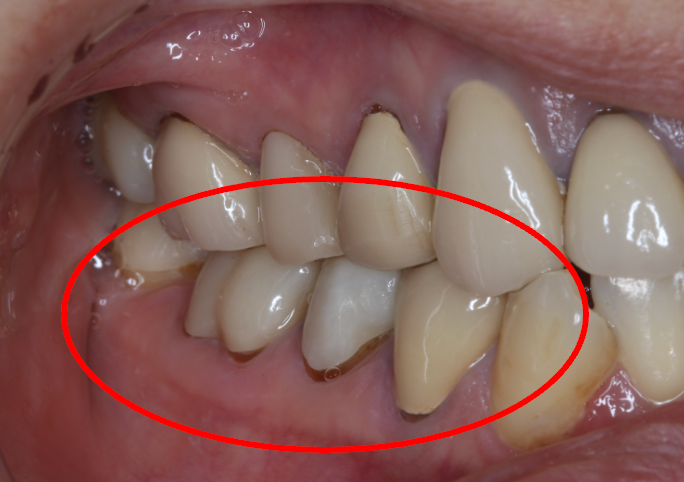

セラミック症例③

年齢30代女性

治療期間1ヶ月

治療内容セラミックインレー

治療箇所右下4番

治療費用100,000円